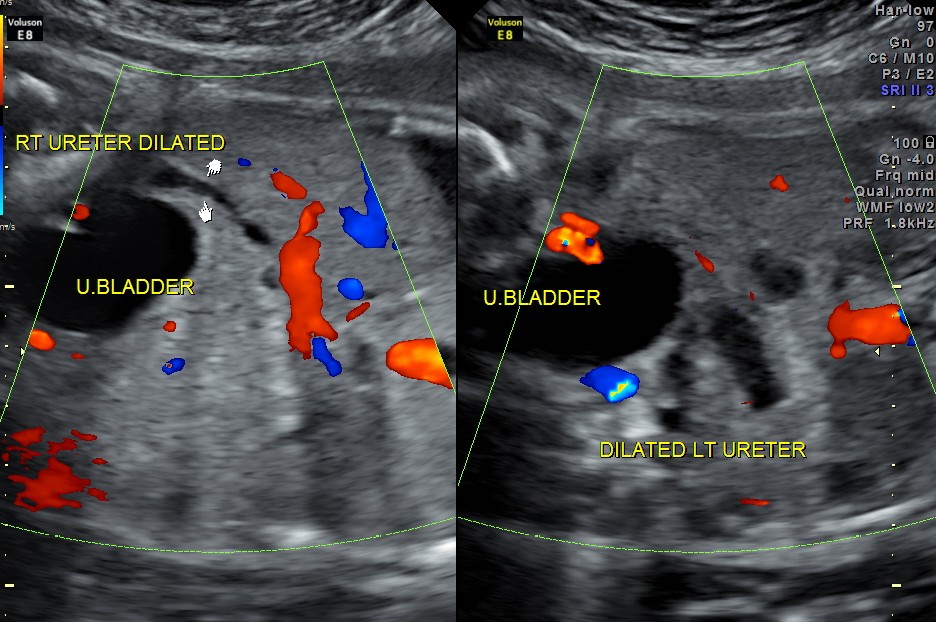

The following images show bilateral renal pelvi ectasis and bilateral dilated ureters with all the changes more in the left kidney .

The left kidney also showed possible duple-ix pelvis with double ureters arising from them . But this finding could not be confirmed in all the views .